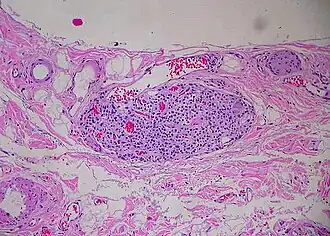

Paraganglion of gallbladder

A paraganglion (pl. paraganglia) is a group of non-neuronal cells derived of the neural crest. They are named for being generally in close proximity to sympathetic ganglia. They are essentially of two types: (1) chromaffin or sympathetic paraganglia made of chromaffin cells and (2) nonchromaffin or parasympathetic paraganglia made of glomus cells. They are neuroendocrine cells, the former with primary endocrine functions and the latter with primary chemoreceptor functions.[1]

Chromaffin paraganglia (also called chromaffin bodies) are connected with the ganglia of the sympathetic trunk and the ganglia of the celiac, renal, adrenal, aortic and hypogastric plexuses. They are concentrated near the adrenal glands and essentially function the same way as the adrenal medulla. They are sometimes found in connection with the ganglia of other sympathetic plexuses. None have been found with the sympathetic ganglia associated with the branches of the trigeminal nerve. The largest chromaffin paraganglion is the organ of Zuckerkandl, it is probably the largest source of circulating catecholamines in the fetus and young infants, and gradually atrophies to microscopic loci.[1]

Nonchromaffin paraganglia include carotid bodies and aortic bodies, some are distributed in the ear, along the vagus nerve, in the larynx and at various other places.[2]